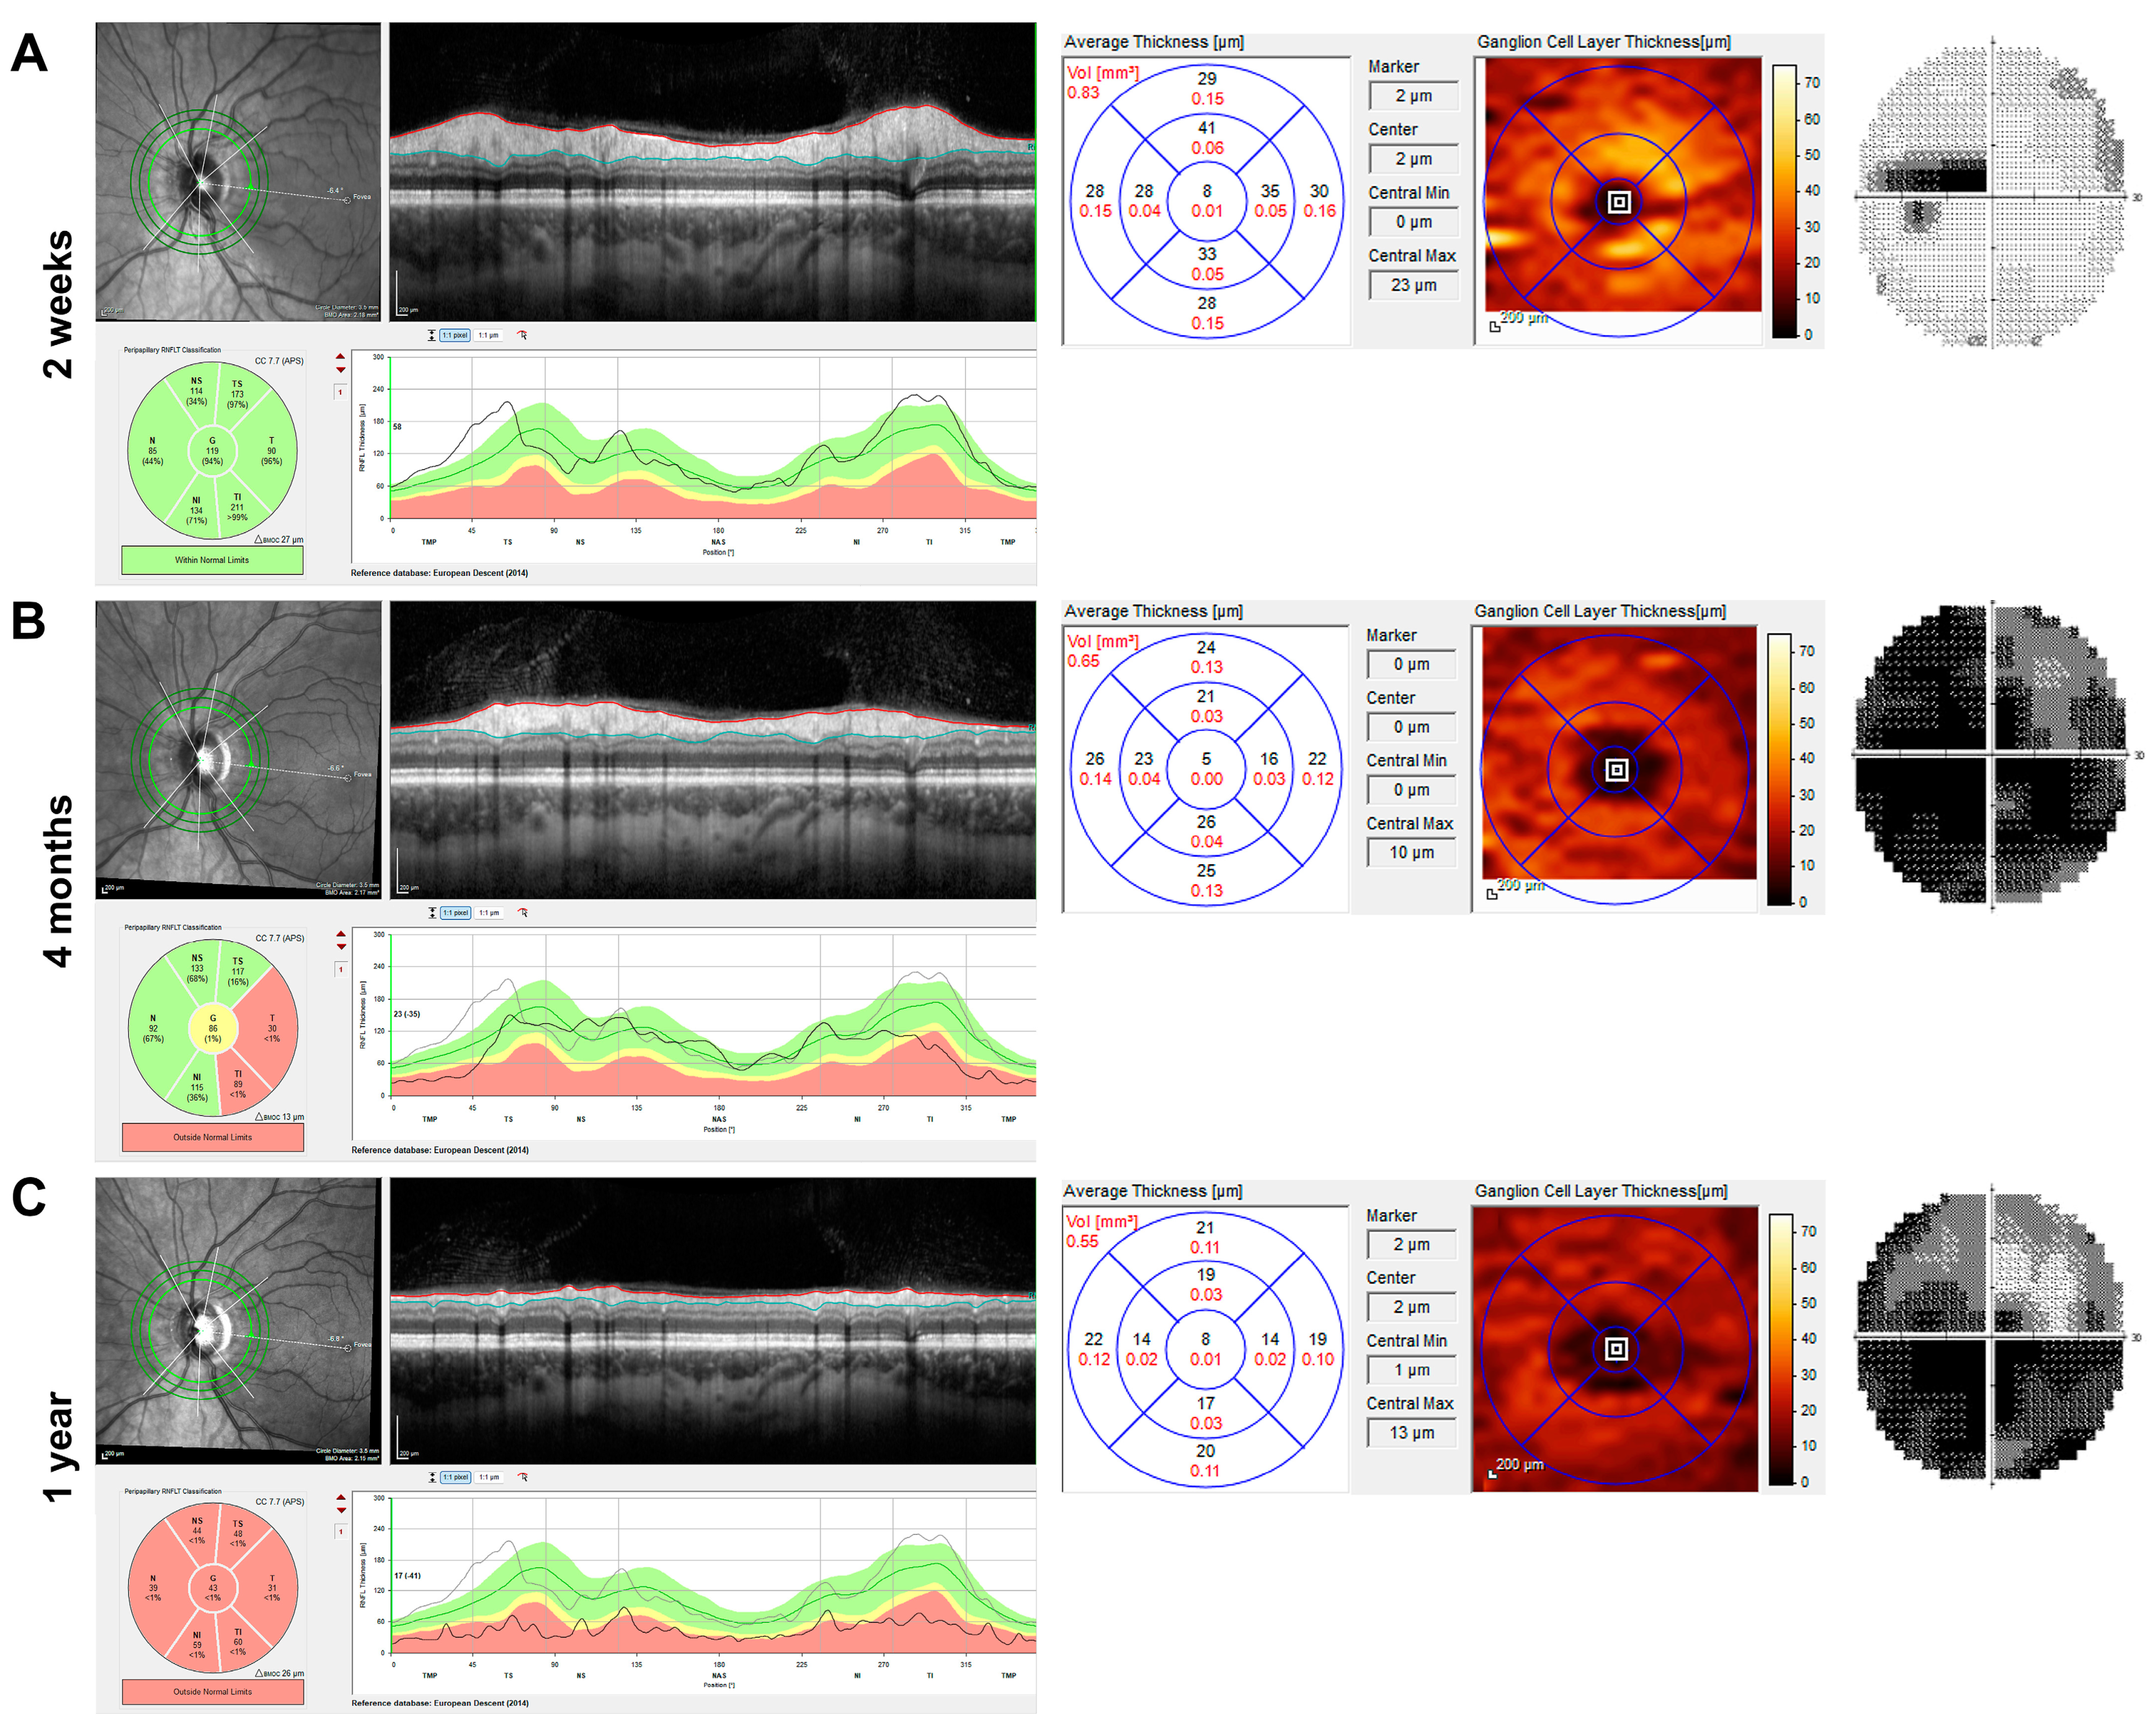

Among the LHON patients, two patients received two OCT scans during the first year, two received three scans, two received four scans, and one patient each received five, six, and seven scans, respectively. Among the optic neuritis patients, nineteen patients received two scans, and one patient received three scans. The normally doughnut-shaped GCL showed a significant reduction in thickness soon after vision loss in LHON patients (Figure 2 shows the OCT and visual field of a representative patient two weeks, four months, and one year after vision loss), whereas the RNFL appeared preserved or supernormal in the first weeks (2A) and continuously atrophied during the first year.

Figure 2. Imaging and visual field of the left eye of a 25-year-old Leber hereditary optic neuropathy (LHON) patient with m.11778G→A mutation during the first year after the onset of symptoms. Analysis of retinal nerve fibre layer (RNFL) and macular ganglion cell layer thickness (GCLT) by spectral-domain optical coherence tomography (SD-OCT, Heidelberg Engineering, Heidelberg, Germany) and Humphrey visual field (30-2, Analyser 3, Zeiss, Jena, Germany) are shown from left to right for three time points. (A) Two weeks after symptom onset, there was subtle swelling of the peripapillary RNFL, but already reduced GCLT in all sectors, particularly in the nasal foveal region. Centrocecal scotoma was present, and the visual acuity was 0.80 log MAR at this time. (B) At four months, the RNFL was partially reduced, especially in the temporal region, but there were hardly any ganglion cells visible in the colour image of the GCLT analysis. Almost complete loss of the central visual field was observed over the months. (C) One year after the onset of symptoms, circular atrophy of the RNFL and further reduction in the GCLT were observed with visual field depression, showing enlarged fenestration in the upper visual field.